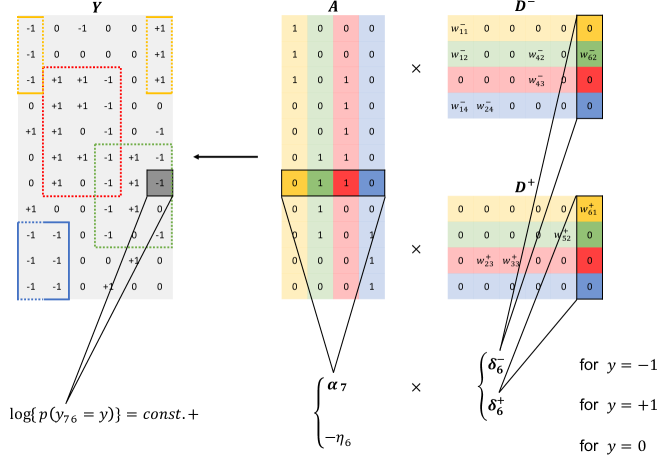

Categorical matrix factorization (CMF). DFA can be viewed as a CMF. Merging and , model (5) probabilistically factorizes an categorical matrix into an low-rank binary matrix and an low-rank nonnegative matrix where , , and . From (5),

where , , with element-wise multiplication , and . Figure 3 illustrates the factorization. The matrix describes the PD relationships. and characterize the SD relationships where and . The number of diseases is less than the number of patients and the number of symptoms.